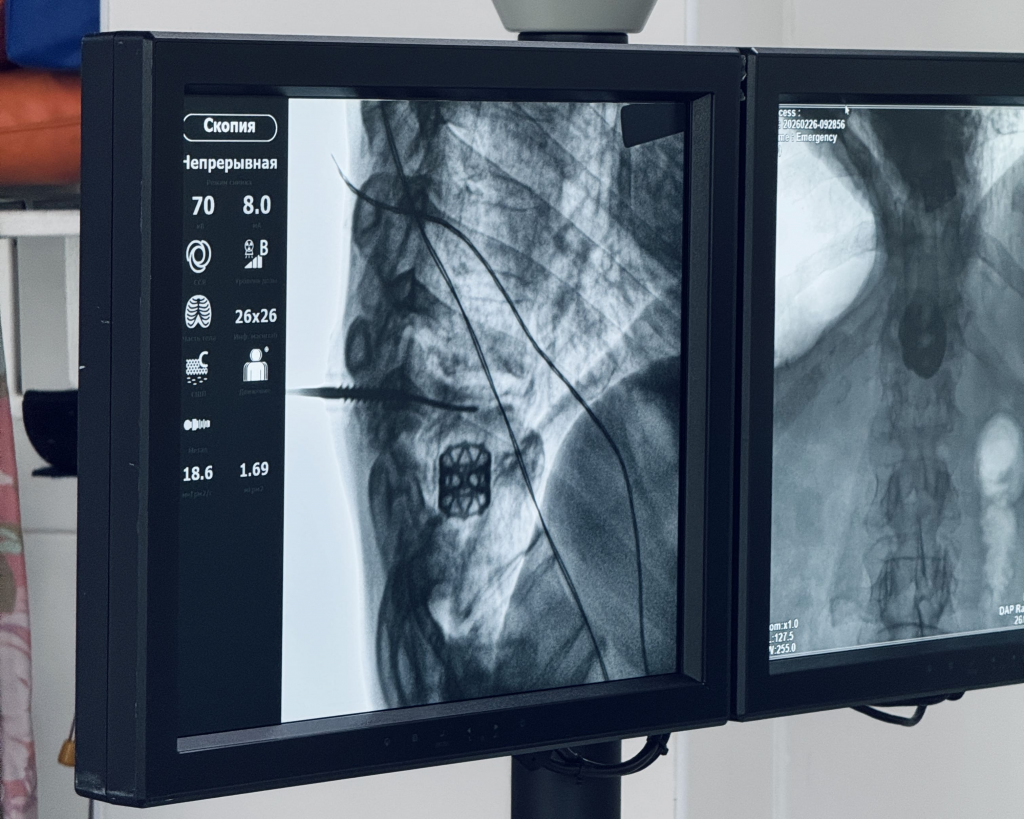

Обследование подтвердило воспалительное поражение межпозвонковых дисков, которое привело к нарушению оси позвоночника и его выраженной деформации. Ключевой задачей для нейрохирургов стал выбор метода, который одновременно обеспечил бы надёжную стабилизацию позвоночника и исключил риск распространения инфекции. Чтобы помочь пациенту, специалисты использовали отечественную систему: её полые внутри винты устанавливаются по тонкой направляющей спице, обеспечивая точность позиционирования имплантов и минимальное повреждение мягких тканей.